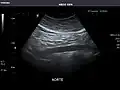

Abdominal Ultrasound (Full Exam)

STRUCTURED REPORT

(Technique: Transabdominal ultrasonography; Device: Toshiba Aplio XG)

Aorta: Visualized portions normal in caliber, 16 x 15 mm.

IMPRESSION:

Normal abdominal ultrasound.

-

Aorta -